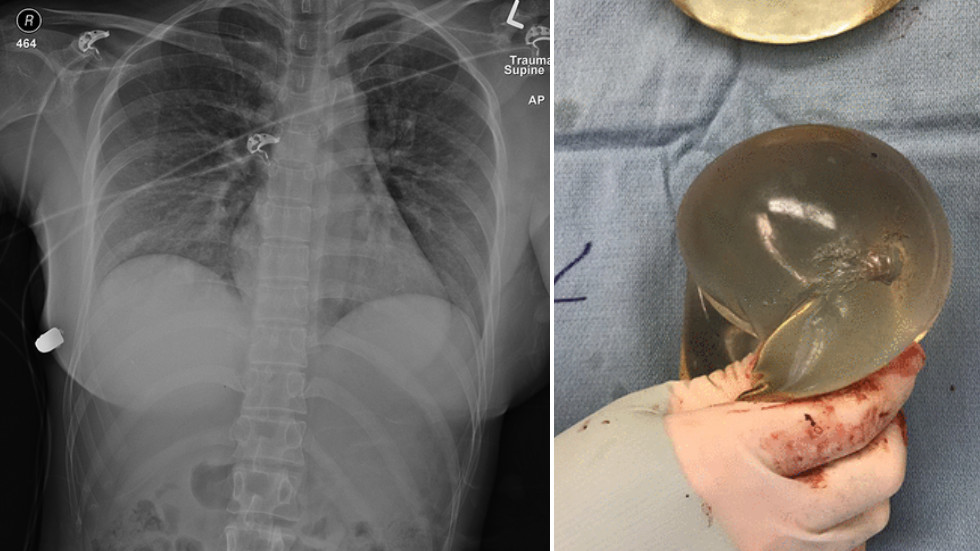

Ekipi mjekësor zbuloi një plagë të vetme hyrëse në pjesën e sipërme të gjoksit të saj të majtë; shenjat e djegies përreth plagës treguan se gruaja ishte qëlluar në distancë të afërt.

Plumbi ishte nën gjoksin e saj të djathtë, pasi kishte hyrë në gjoksin e majtë, duke thyer një brinjë përpara se të ndalonte në anën e djathtë të zgavrës së saj të gjoksit.

“Implanti ishte vendosur sipër zemrës dhe prandaj i shpëtoi jetën pacientes.” – thanë mjekët e spitali.